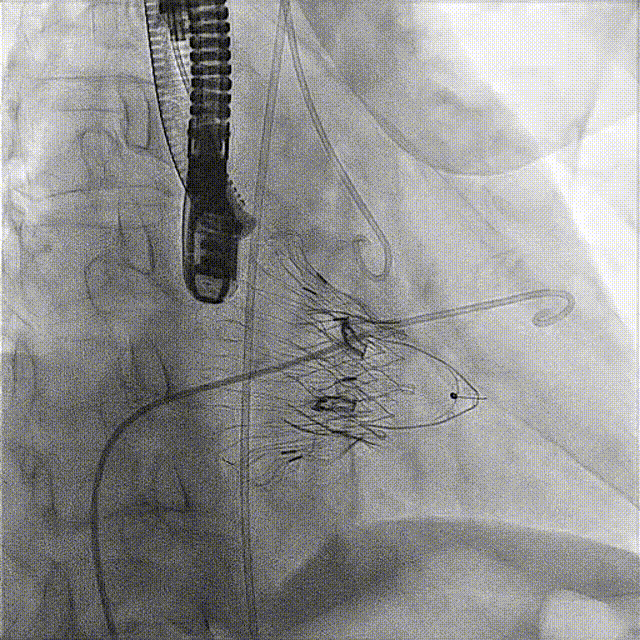

術(shù)后DSA

術(shù)前經(jīng)過(guò)全面系統(tǒng)的評(píng)估后,考慮患者存在高齡、心功能減低、三尖瓣瓣環(huán)重度擴(kuò)張(三尖瓣極重度反流)等高危因素,因此廈心結(jié)構(gòu)心團(tuán)隊(duì)聯(lián)合超聲心動(dòng)、麻醉及護(hù)理團(tuán)隊(duì),制定了詳盡的圍術(shù)期治療方案及術(shù)中治療難點(diǎn)預(yù)案。術(shù)中,由王焱院長(zhǎng)主刀,在蘇茂龍主任超聲心動(dòng)團(tuán)隊(duì)的輔助,上海市第一人民醫(yī)院陸方林主任的協(xié)助下,僅用時(shí)30分鐘,即順利完成了三尖瓣原位置換的手術(shù)。術(shù)中患者血流動(dòng)力學(xué)穩(wěn)定,術(shù)后即刻顯示LuX-Valve Plus瓣膜位置良好,固定穩(wěn)定,瓣膜功能正常,無(wú)瓣周漏。